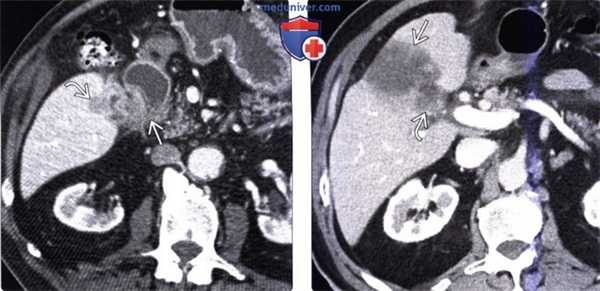

(Левый) У женщины 37 лет с острыми болями в правом верхнем квадранте живота на сагиттальном УЗ срезе желчного пузыря визуализируются отбрасывающие тень конкременты и сладж, а также опухолевидное дольчатое локальное утолщение стенки, прорастающее трансмурально.

(Правый) При КТ с контрастным усилением в режиме мульти планарной реконструкции в той же сагиттальной плоскости определяется полипоидное объемное образование стенки желчного пузыря, накапливающее контраст.